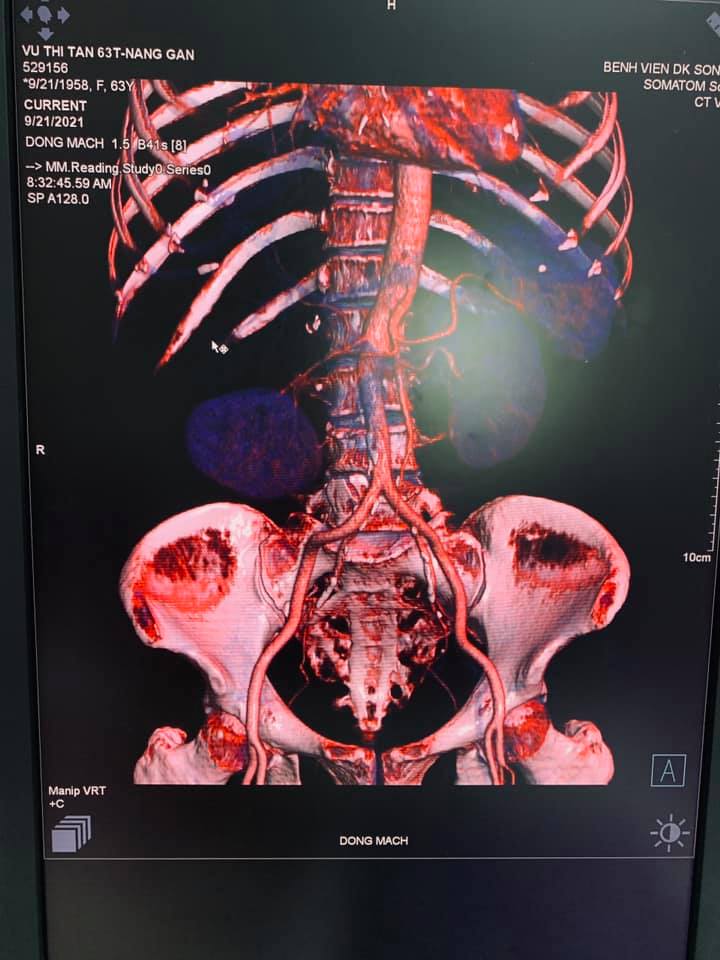

Qua hỏi bệnh, thăm khám và làm các xét nghiệm chẩn đoán cận lâm sàng được biết bệnh nhân có tiền sử Nang gan phải đã phẫu thuật nang gan 2 lần.( lần 1 năm 2019, lần 2 năm 2021), Xét nghiệm huyết học, sinh hóa các trị số bình thường, kết quả siêu âm: Hình ảnh nang gan phải TD xuất huyết trong nang, kết quả chụp cắt lớp vi tính : Hình ảnh nang gan chảy máu( KT 11x12cm).